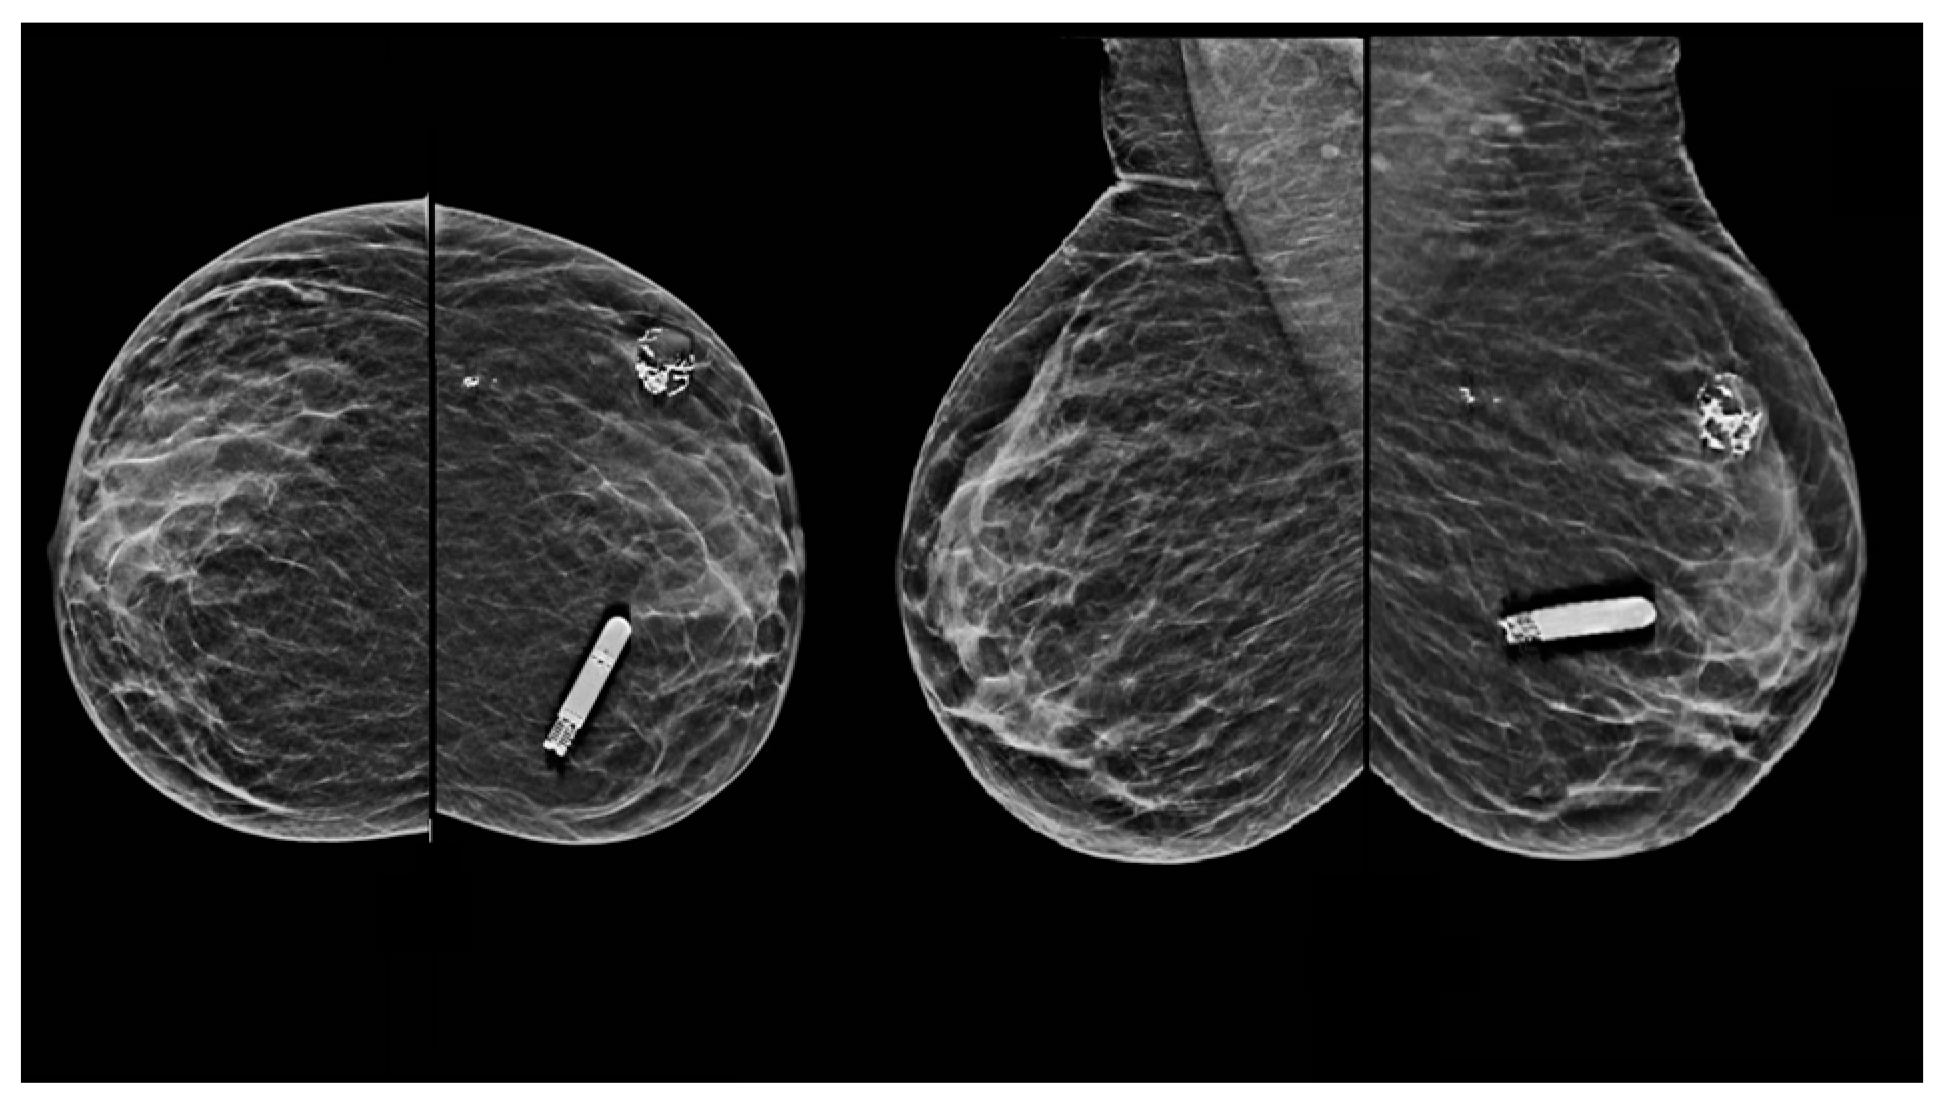

Comparison of Visual and Quantra Software Mammographic Density Assessment According to BI-RADS® in 2D and 3D Images

2.2. Image Acquisition

2.3. Software for Automatic Breast Density Assessment